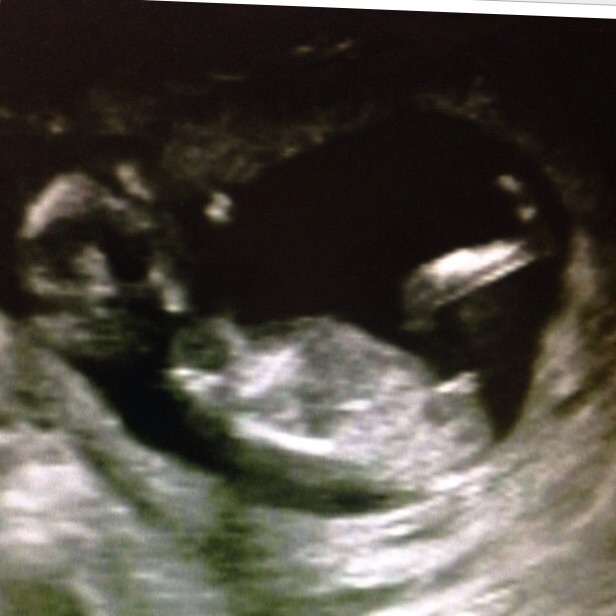

I think girl because you're already 14 weeks and the nub is quite parallel to the spine, it won't be rising any more. But it does look a bit like a boy nub too, so don't buy pink from my prediction :) Also I see no sign of a penis on the potty shot, although there is a lot of "noise" around the potty area, so that could theoretically be a penis. I hope you hear girl. When is your next scan?

Are the lines part of the nub or something else?

Girl lean.